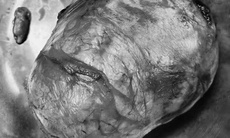

Sau khi thăm khám và làm các cận lâm sàng chuyên sâu, các bác sĩ xác định khối u xơ tử cung có kích thước khoảng 8cm, thuộc loại 3-5, dạng u xơ dễ gây biến chứng rong kinh, cường kinh, khó kiểm soát bằng nội khoa nên tư vấn phẫu thuật.

Ca phẫu thuật được tiến hành ngay tại Bệnh viện Đa khoa Sài Gòn. Khối u được bóc tách hoàn toàn, tử cung được bảo tồn, người bệnh không mất nhiều máu và hồi phục tốt. Sau 4 ngày, chị H. được xuất viện trong tình trạng ổn định.

BS.CKII Hứa Thị Chi - Khoa Sản bệnh, Bệnh viện Nhân dân Gia Định cho biết: “Trường hợp của chị H. với khối u lớn, loại 3-5, nếu không phẫu thuật, có thể dẫn đến rong kinh, cường kinh, thiếu máu nặng, thậm chí ảnh hưởng nghiêm trọng đến khả năng mang thai. May mắn là người bệnh còn trẻ, tử cung chỉ có một khối u duy nhất, có ranh giới rõ nên chúng tôi quyết định bóc u, bảo tồn tử cung”.